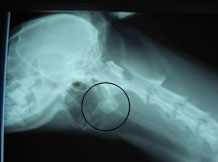

45-03

45-05

除去後のレントゲン写真。異物は除去されている。